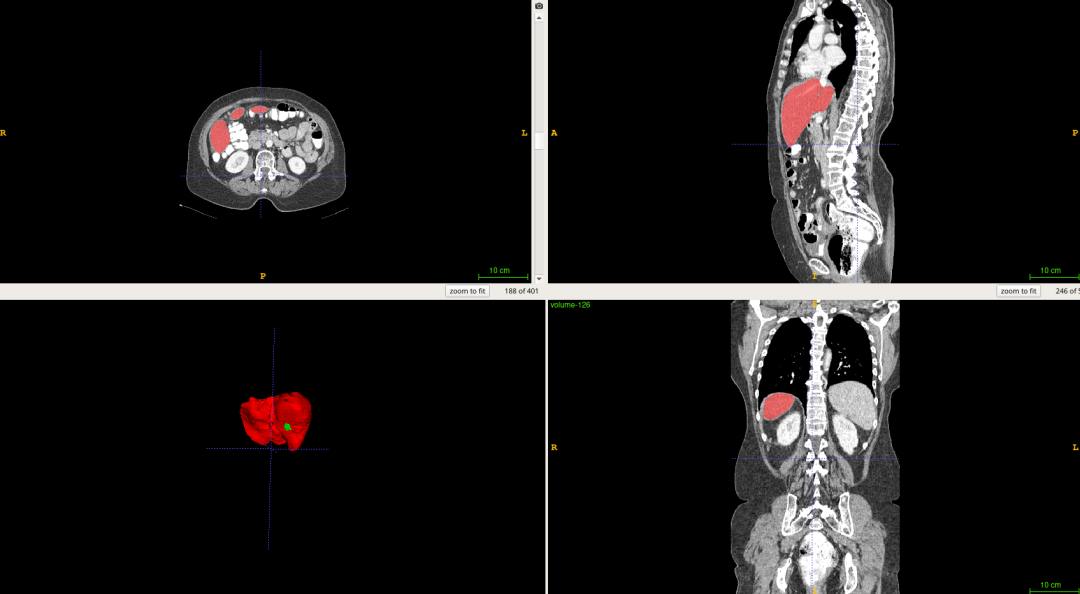

基于飞桨PaddlePaddle框架,我使用Res-Unet网络结构在 LiTS 数据集[2]上训练了一个分割网络,最终在肝脏和肝肿瘤上分别达到了 0.92 和 0.77 的分割 准确率 。LiTS数据集是目前最大的开源肝脏分割数据集,其中包含130名患者的CT扫描和医生对患者肝脏及肿瘤的分割标注,下图是数据集中的一个示例:

图1 肝脏分割示例项目在AI Studio上公开,提供包含数据集在内的完整环境,fork后可以直接运行。

图6 分割结果 深度学习 算法对一组CT扫描进行分割大概耗时15S,其效率明显高于医生阅片的效率。而且从分割结果中,我们可以计算获得肝脏体积,肿瘤数量,肿瘤体积,肝脏肿瘤负担等数 量化 的指标,更好地辅助医生进行诊断。